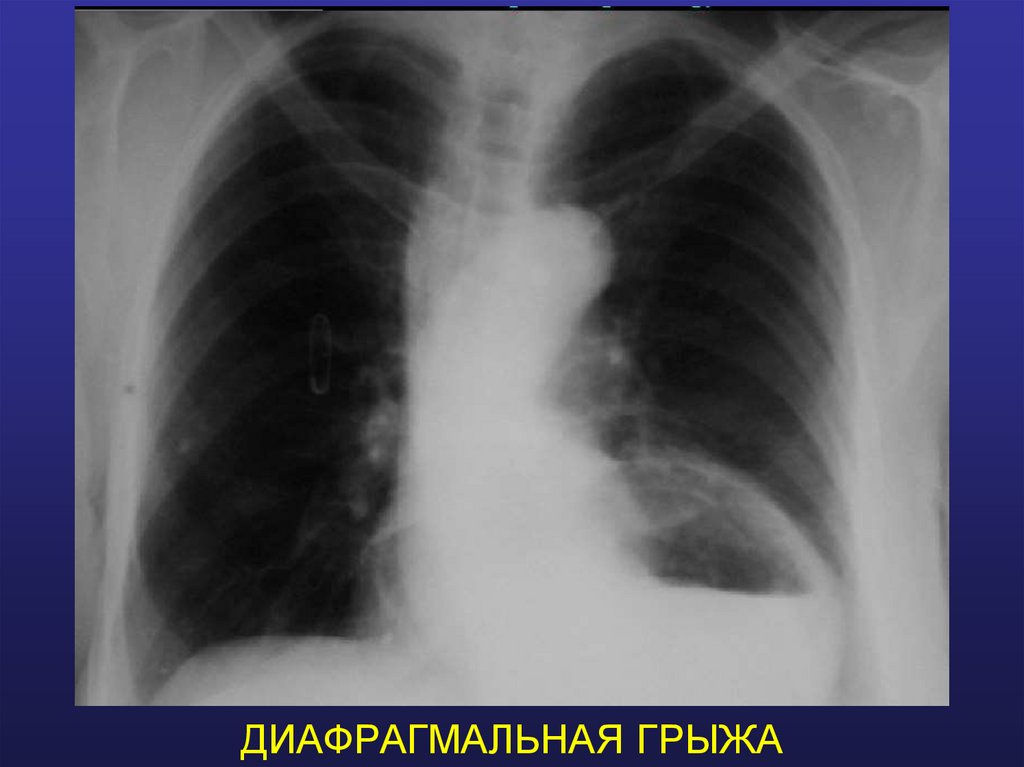

ДИАФРАГМАЛЬНАЯ ГРЫЖА

32. ДИАФРАГМАЛЬНАЯ ГРЫЖА

Разрыв диафрагмы.